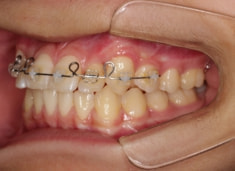

治療法:上顎急速拡大装置+クリアスナップ+フェイスマスク+上顎3番は開窓牽引CT写真にて位置確認

治療開始時